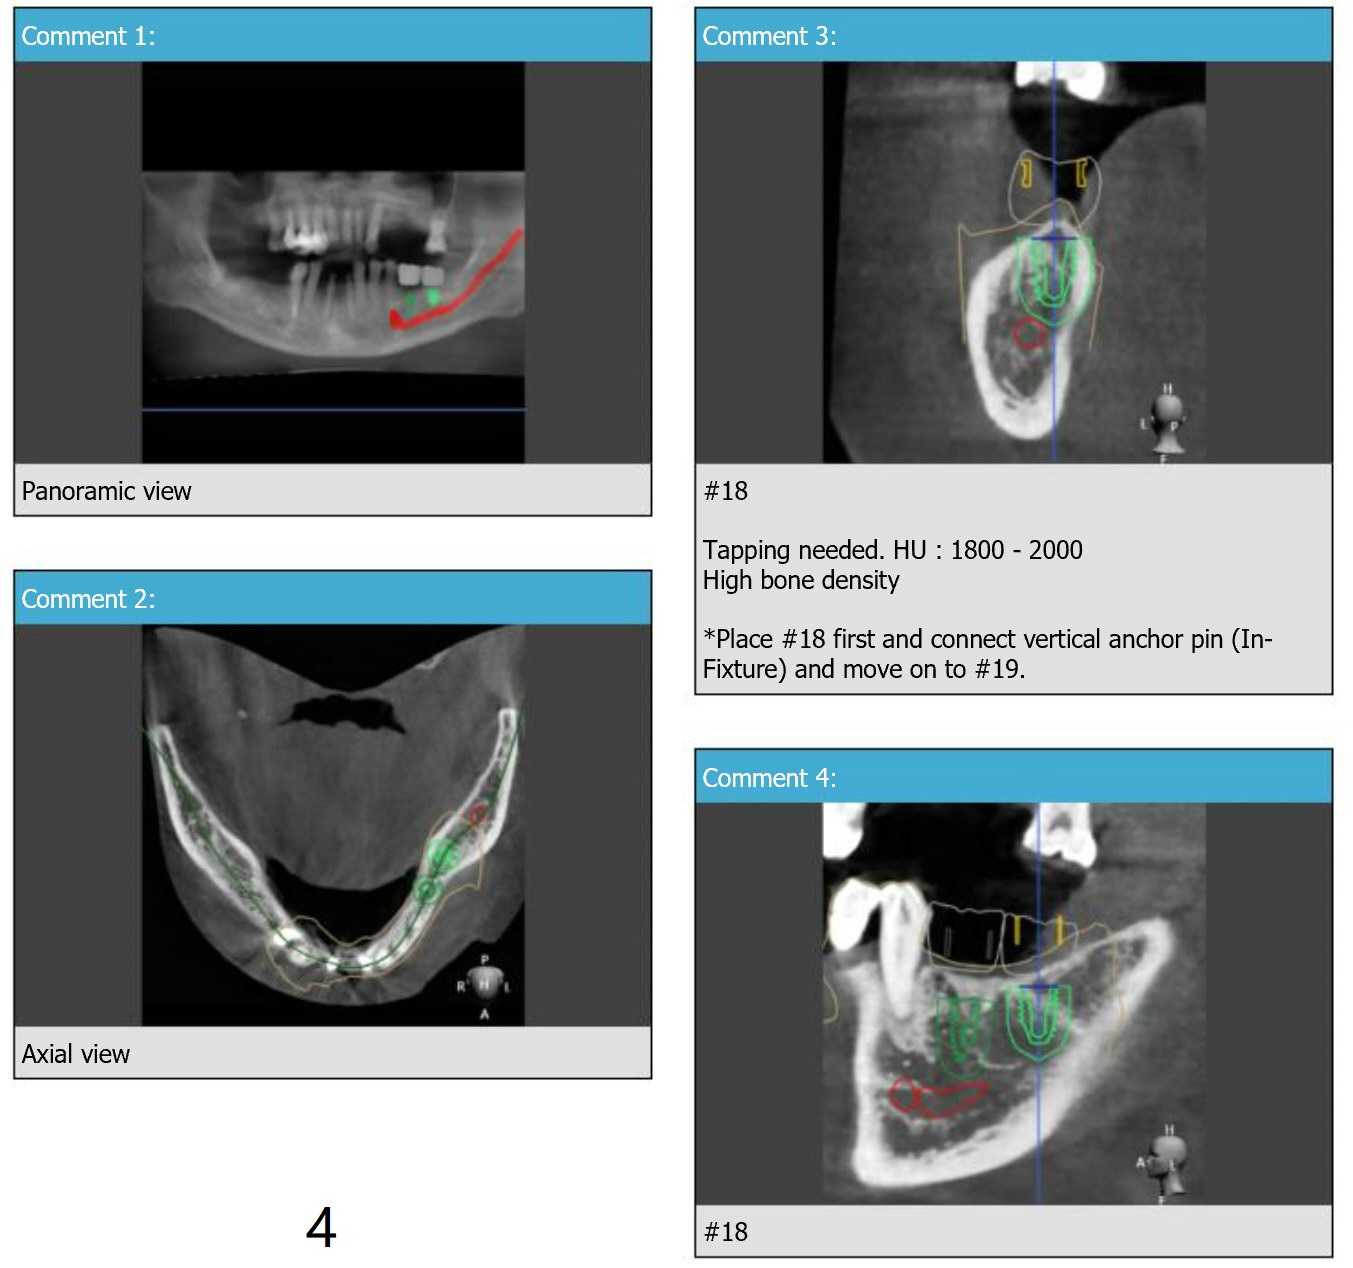

Fixture Anchor Pin at #18

Return to Lower Molar Immediate Implant Armaments  Placement